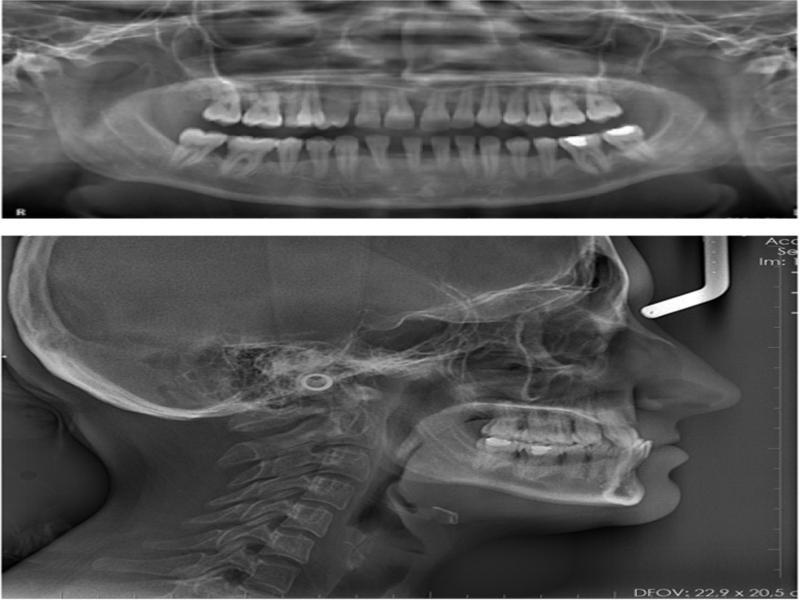

Figure 2.